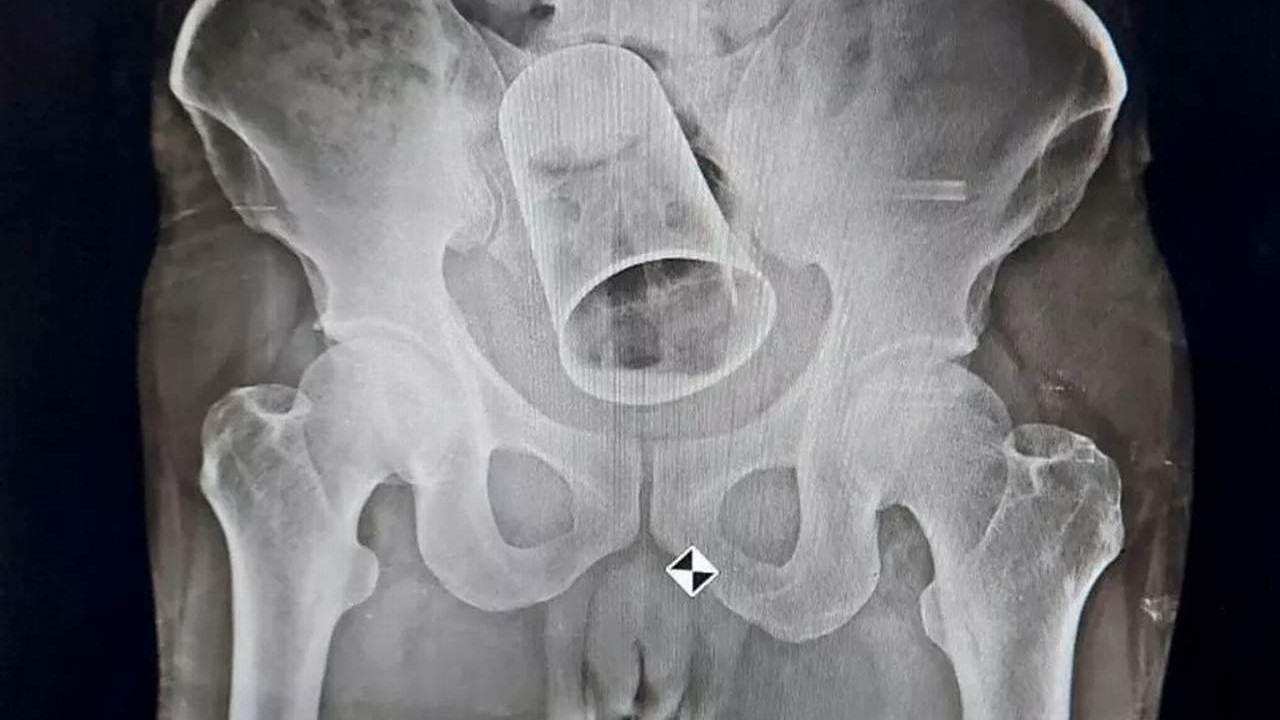

Hindistan'ın Balipadar kentinde yaşanan olayda; arkadaşları, sarhoş bir durumda olan 45 yaşındaki adamın arka tarafına çelik kupayı soktu ve onu yerel bir hastanedeki doktorlardan yardım almaya zorladı. Çekilen röntgenden sonra, doktorlar çelik bardağı bağırsakta sıkışmış halde buldu.

Doktorlar bardağı rektumdan almaya çalıştı ancak girişimleri başarısız oldu. 45 yaşındaki adamı operasyona aldılar. Operasyonda çelik bardağı çıkardır. Durumu stabil olan adam sonrasında sağlığına kavuştu.